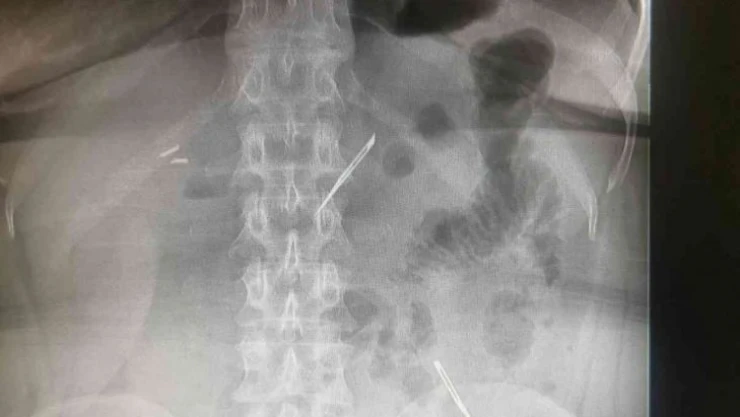

Sağlık Bilimleri Üniversitesi Ankara Atatürk Sanatoryum Eğitim ve Araştırma Hastanesi’ne mide ve karın bölgesinde aşırı ağrı şikayeti ile müracaat eden 46 yaşındaki D.E.’nin yapılan tahlil, tetkik ve çeşitli görüntülemelerden sonra bağırsak kısmında 2 adet neşter olduğu tespit edildi. Genel cerrahi kliniği tarafından zorlu bir ameliyat sonrasında neşterler kadının vücudundan çıkarıldı. 46 yaşındaki D.E. neşterleri nasıl yuttuğunu bilmediğini tahminen ekmek ile birlikte yutabilmiş olabileceğini ifade etti. Ameliyatı gerçekleştiren Sağlık Bilimleri Üniversitesi Ankara Atatürk Sanatoryum Eğitim ve Araştırma Hastanesi Genel Cerrahi Kliniği Eğitim ve İdari sorumlusu Prof. Dr. Hakan Buluş ise hastanın yoğun şikayetleri üzerine çektikleri röntgen sonrasında 2 adet neşteri görünce şaşkına uğradıklarını söyledi.

Hastanın şikayetlerinin artması üzerine gerçekleştirilen tetkiklerde 46 yaşındaki kadının karın bölgesinde 2 adet yabancı cisim olduğunu tespit ettiklerini, detaylı inceleme sonucunda bu cisimlerin neşter olduğunu fark ettiklerini belirten Prof. Dr. Buluş, “Yaklaşık 10 gün önce kliniğimize karın ağrısı ve bulantı şikayetleri ile başvurdu. Bizim yaptığımız fiziki muayene ve tetkiklerinde hastanın direkt karın grafisinde 2 adet yabancı cisim olduğunu tespit ettik. Aslında yabancı cisim bizim güncel grafiğimizde sık karşılaştığımız bir durum değil, fakat nadir de olsa görebildiğimiz bir patoloji. Biz de bunun üzerine ayrıntılı değerlendirmeler ve tetkikler yaptık. Sonrasında 2 adet yabancı cismin bistüri (neşter) ile uyumlu olduğunu gördük. Bunun üzerine hastanın şikayetlerinin de artması üzerine, ameliyat kararı verdik. Yaptığımız ameliyatta ince bağırsağın yaklaşık 180’inci santimetresinde bu yabancı cisimlerin olduğunu tespit ettik. Bunun üzerine ameliyatla bunları çıkarttık. Hastamızın sağlık durumu şuan gayet iyi. Ameliyattan sonraki üçüncü günü. Şuan bir problemi yok, inşallah birkaç gün içerisinde şifa ile taburcu etmeyi düşünüyoruz” şeklinde konuştu.

Çıkardıkları cismin, neşterin normalde ameliyatlarda kullanılan bir malzeme olduğunu söyleyen Prof. Dr. Buluş, “Çıkardığımız yabancı cisimler bizim ameliyatlarda sıkça kullandığımız 11 numara dediğimiz bir bistüri tipi. Ebatları da yaklaşık 4 santime yarım santim ebatlarında. Ucunun sivri olması nedeniyle ince bağırsak mukozasına saplanarak enflamasyon ve bir karın ağrısı yapması, sonrasında da ağrı şikayetlerinin artmasına neden olmasından dolayı ameliyat kararı verdik” diye konuştu.